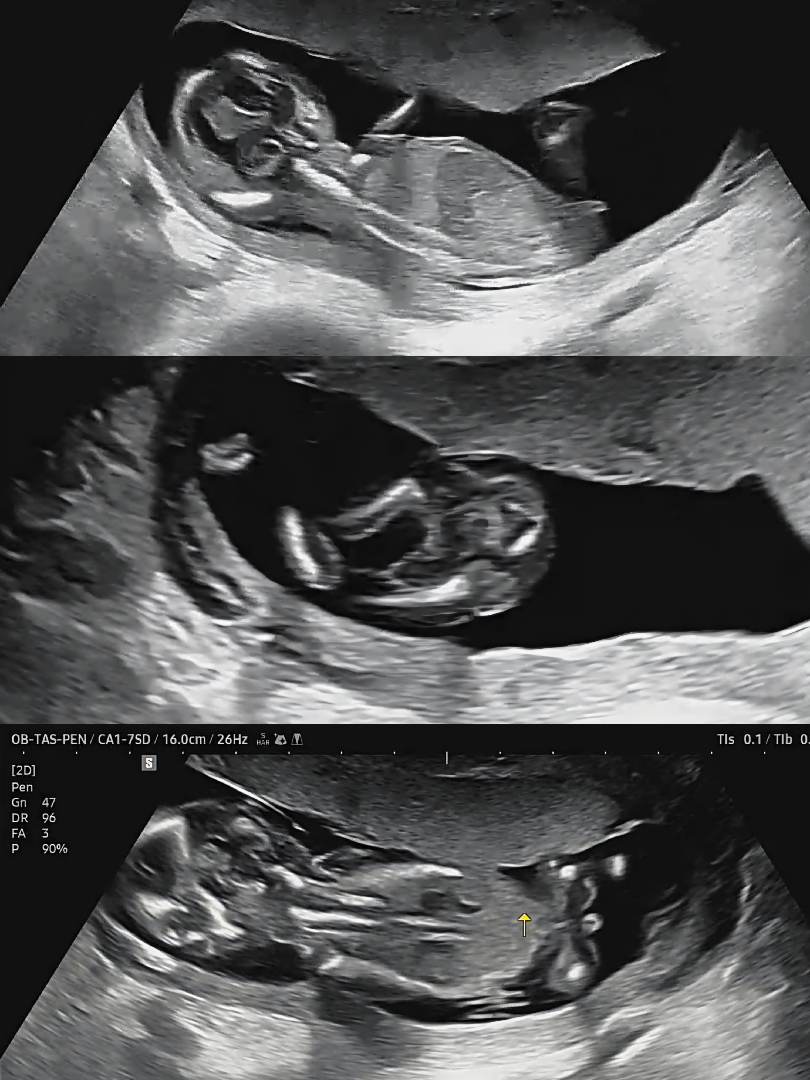

14w2d) 딸 초음파 잘 보시는 분 계실까요?

담당선생님께선 다리 사이 보시고 깨끗하다며 딸 같다고 말씀해주셨는데, 한 번 봐주세요 🙏🏻🤍